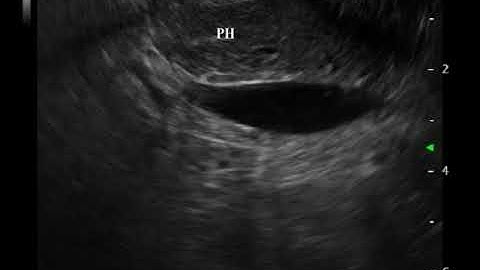

Linear EUS: Penetrating Duodenal Mass